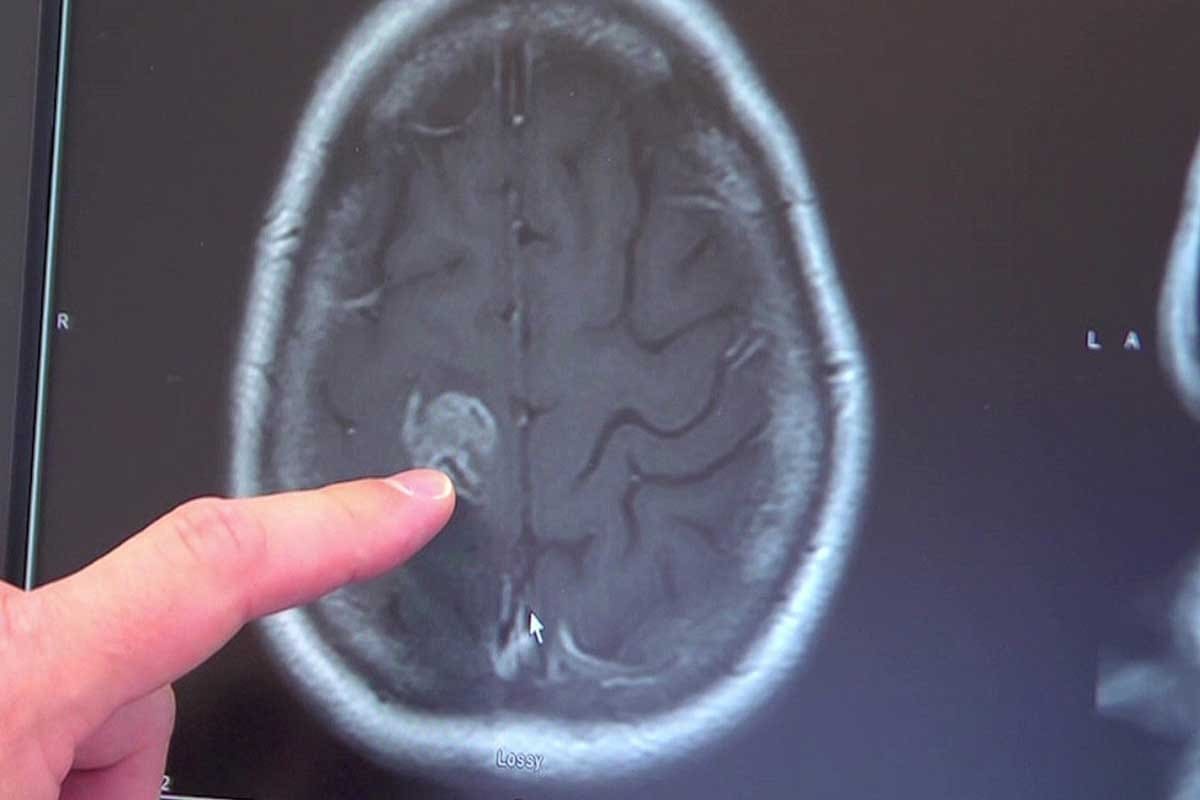

Pre-surgical Consultations and Imaging

Before surgery, patients have many tests and talks with doctors. These steps help doctors plan the surgery. Tests like MRI or CT scans show the surgeon what needs to be fixed.